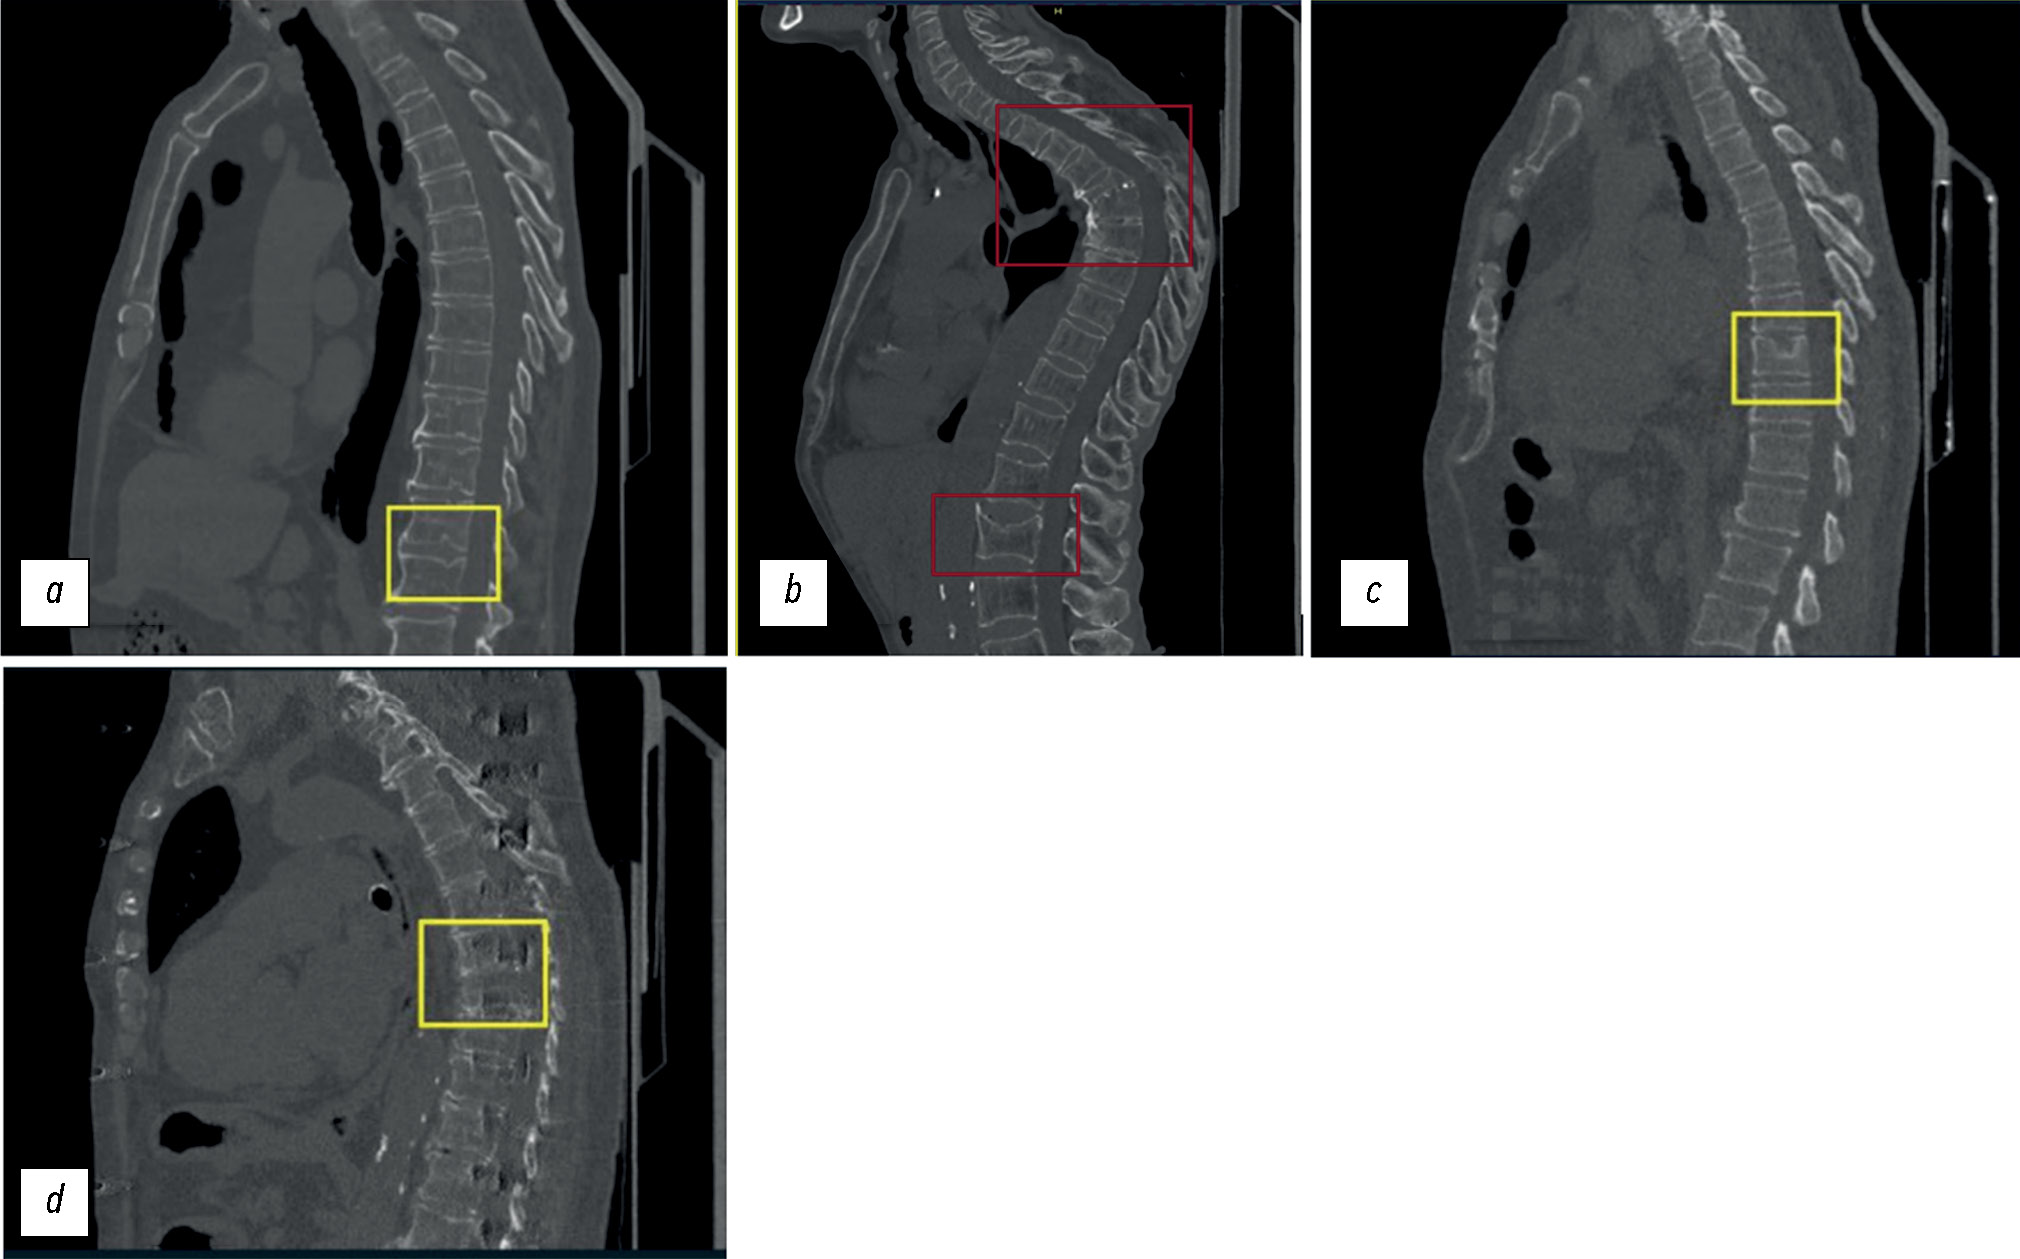

ИИ-сервис № 2 осуществляет полуколичественную оценку. Данный сервис также основан на свёрточных нейронных сетях с последующим использованием рекуррентной нейронной сети для прогнозирования наличия деформации тела позвонка (рис. 3) [21]. Результат работы ИИ-сервиса № 2 представляется в виде трёх строго сагиттальных срезов (что позволяет визуализировать целевую патологию у пациентов со сколиозом), на которых отмечено тело позвонка с максимальной деформацией (см. рис. 3). При отсутствии деформации в дополнительной серии отображается надпись: «Целевая патология не обнаружена».

Рис. 3. Примеры работы сервиса HealthVCF: дополнительная серия компьютерного томографического исследования с разметкой целевой патологии — компрессионного перелома.

Рис. 6. Примеры ошибок работы сервиса Genant-IRA: a — ложноположительный результат: сервис отметил обызвествлённый межпозвонковый диск ThXI–ThXII как тело позвонка ThXII с компрессионной деформацией >40% (Genant 3); b — ложноположительный результат: сервис отметил выраженный остеофит LI как тело позвонка ThXII с компрессионной деформацией >40% (Genant 3), при этом тело позвонка ThXII не размечено; c — ложноположительный результат: у пациента с выраженным сколиозом произошло критическое нарушение работы алгоритма (так называемый слом алгоритма), нарушение построения криволинейной реконструкции, как следствие — некорректная разметка позвонков и оценка степени их компрессионной деформации; d — ложноположительный результат: ошибочно проведена разметка и выявлена компрессионная деформация >40% (Genant 3) «тел» позвонков ThVII и ThVIII вследствие выраженных ring artefacts из-за неисправности детектора компьютерного томографического сканера. Данные о дефекте сканера переданы в техническую службу Департамента здравоохранения города Москвы.

Рис. 7. Примеры ошибок работы сервиса HealthVCF: a — ложноположительный результат и некорректная оценка локализации: отсутствие компрессионной деформации >25%; b — ложноотрицательный результат (вероятнее всего — из-за выраженного кифоза у пациента): сервис не отметил компрессионную деформацию тел позвонков более 25% (ThIV, ThV, ThVI, ThVII, LII), отметки сделаны экспертом (красные рамочки); c — ложноположительный результат: отсутствует компрессионная деформация >25% тела позвонка ThIX с грыжей Шморля; d — ложноположительный результат: сервисом ошибочно выявлена компрессионная деформация >25% тела позвонка ThVIII вследствие выраженных «ring artefacts» из-за неисправности детектора компьютерного томографического сканера. Данные о дефекте сканера переданы в техническую службу Департамента здравоохранения города Москвы.